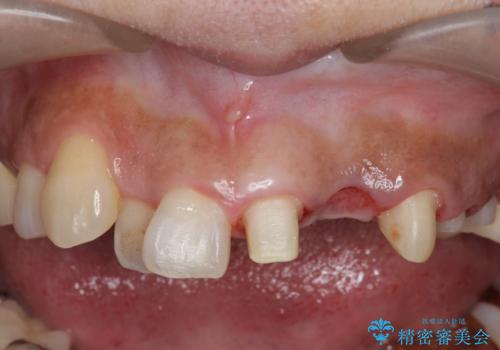

- 左上2番目の歯がグラグラするので診て欲しいといらっしゃった方の症例です。

左上2番目の歯は歯根が破折してため抜歯し、左上123のブリッジによる欠損補綴を行いました。

左上4、5番目の歯は根尖病変を認めたため再根管治療を行い、オールセラミッククラウンによる補綴を行いました。

なお左上4に関しては縁下歯質を改善するため、歯冠挺出を行っております。